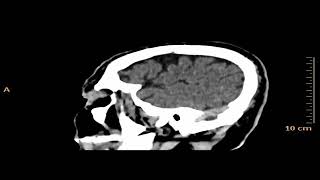

Extradural Vs Subdural Haematomas How Do We...

Acute-On-Chronic Bilateral Subdural Hematoma

Intracranial Hemorrhage Imaging Dr. Cramer